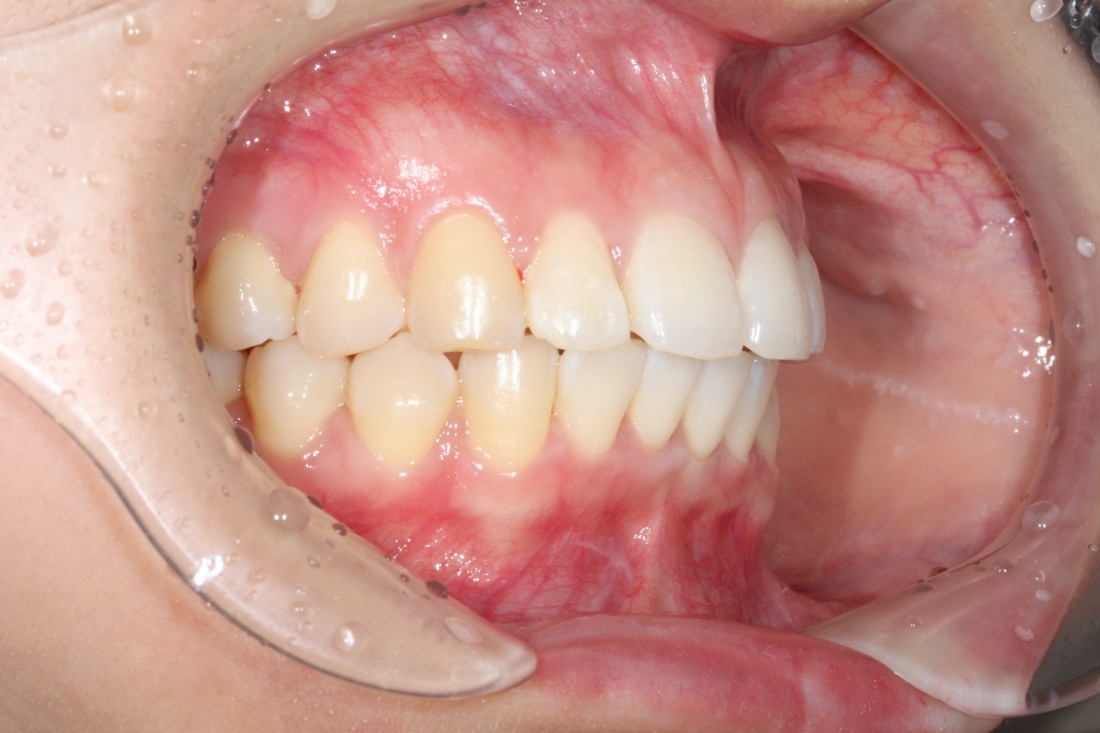

광주 교정치과를 추천하는 이유는

월 진료비가 없는 합리적인 금액으로

광주 치아교정을 받을 수 있기 때문입니다.

치아이동 속도는 개인별로 차이가 크며,

만약 치아 이동속도가 예상보다 늦어질 경우

월 5만원 정도의 월 진료비가

금방 몇 십만원으로 늘어나

비용부담이 크게 다가올 수 있기 때문에

광주 교정치과 추천하는 곳에서는

교정 전 정밀검사 비용

발치비용 (필요시)

교정장치 비용

월 진료비용

유지장치 비용

등 모든 비용을 포함한 금액으로

광주 치아교정을 받을 수 있습니다.